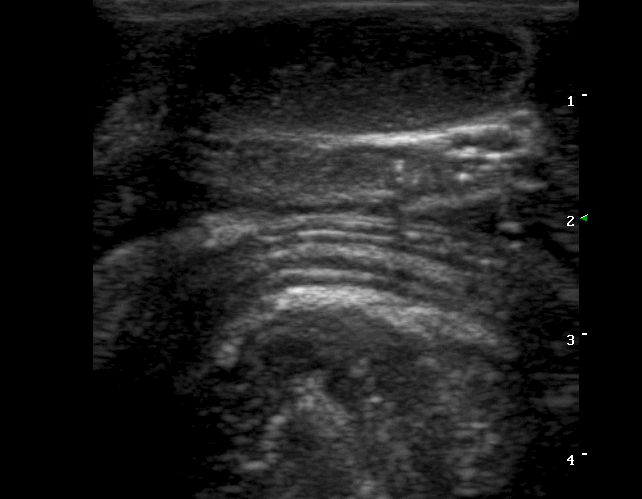

Findings: Distention of large part of the small intestine, caused by intussusception. The blood flow in the mesenteric arteries which supplied the intussusception was normal. The mesenteric lymphnodes were enlarged. A small amount of ascistic fluid was noted.

Ευρήματα: Στον υπερηχοτομογραφικό έλεγχο της κοιλίας βρέθηκε παρουσία εγκολεασμού σε τμήμα του λεπτού εντέρου. Η αιμάτωση των μεσεντέριων αγγείων του εγκολεσθέντος τμήματος εκτιμήθηκε φυσιολογική. Οι μεσεντέριοι λεμφαδένες βρέθηκαν διογκωμένοι με αντιδραστική ηχομορφολογία. Υπήρχε μικρή ποσότητα ασκιτικού υγρού. Οι υπόλοιπες εντερικές έλικες που αφορούσαν το τμήμα του λεπτού εντέρου πριν τον εγκολεασμό βρέθηκαν διατεταμένες .